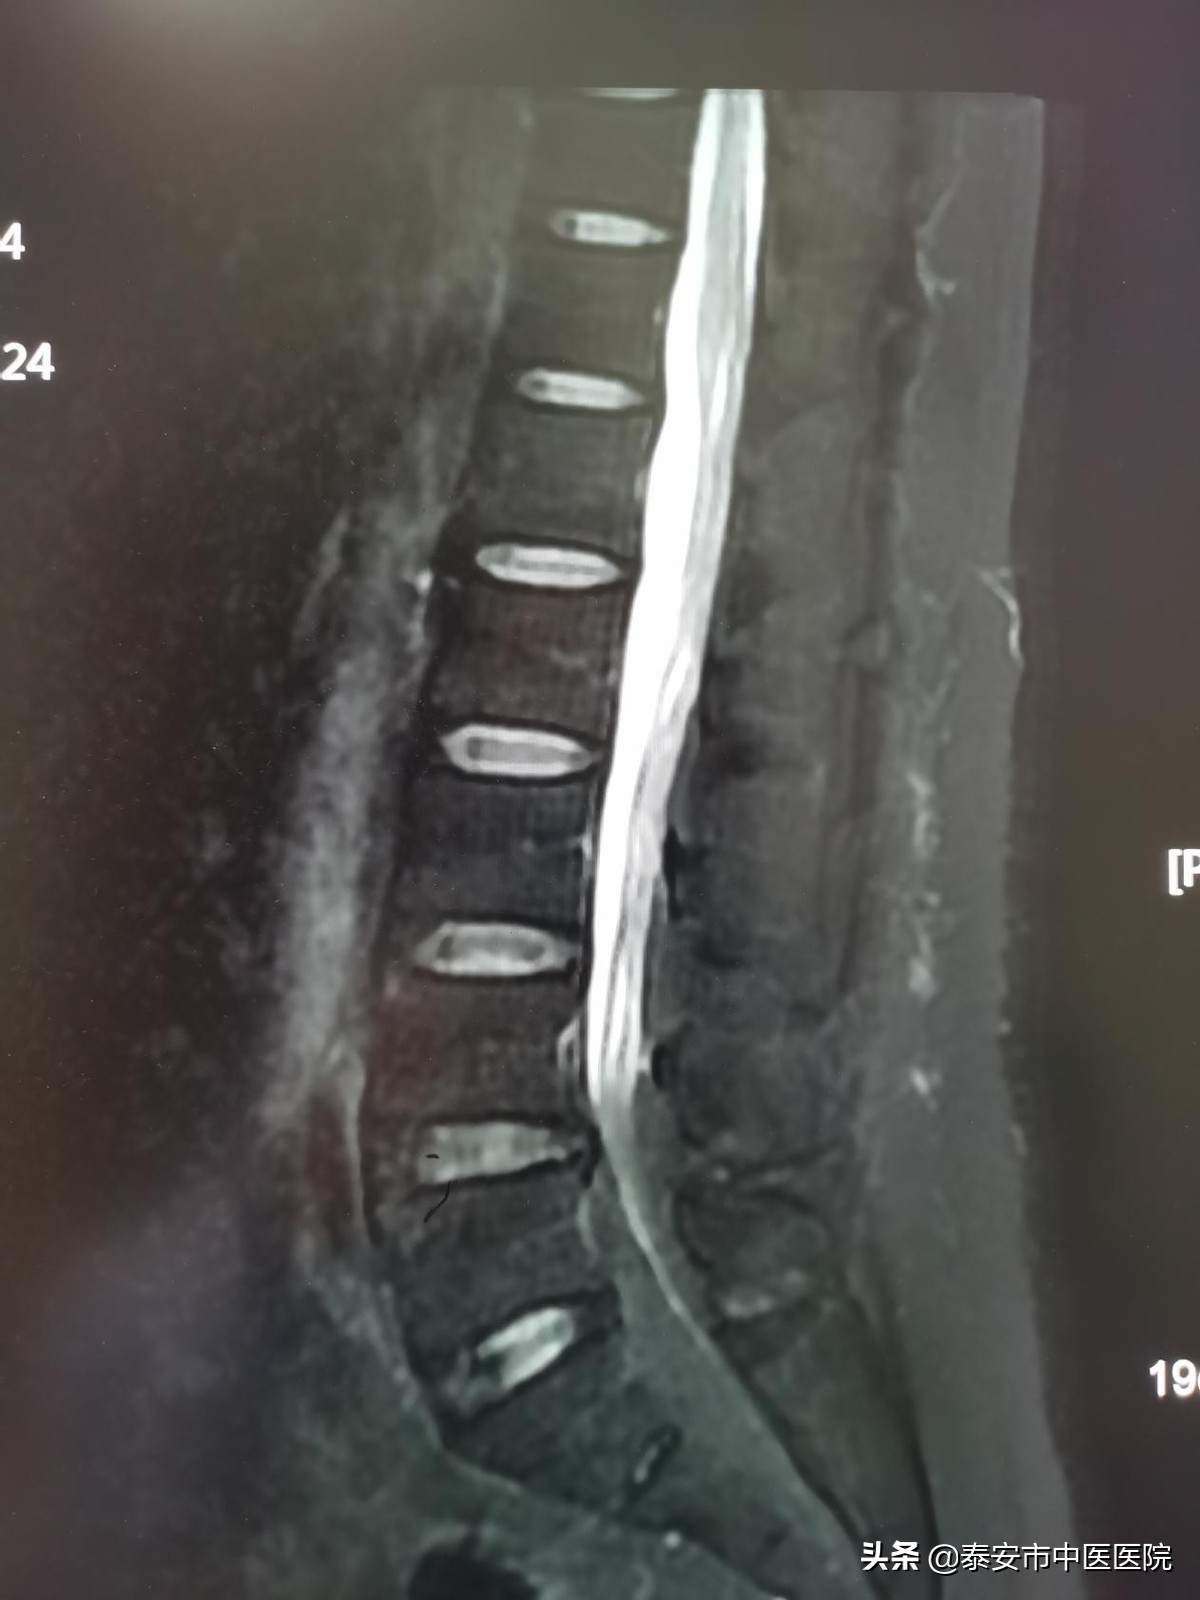

核磁共振结果出来后,脊柱外科全体医生进行了反复讨论,并通过查阅大量文献,终于找到了病因。原来,这是一种比较 罕见的“特发性椎管内硬膜外脂肪增多症” 。正常人的椎管内,都含有少量的脂肪组织。但是王先生的腰椎管内脂肪含量却异常增多,磁共振片子上看到自腰4平面以下椎管内完全填满脂肪组织,对脊髓和神经产生了明显的压迫,因而就会出现相应的神经压迫症状,静息状态下就会有腰腿的麻木、肌力的减弱症状,行走后症状就更加严重,从而严重影响了工作和生活。针对特殊的病情特点,杨明吾制定出了一套行之有效的治疗方案。